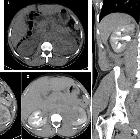

bilateral renal enlargement

Bilateral renal enlargement can arise from a number of causes which include :